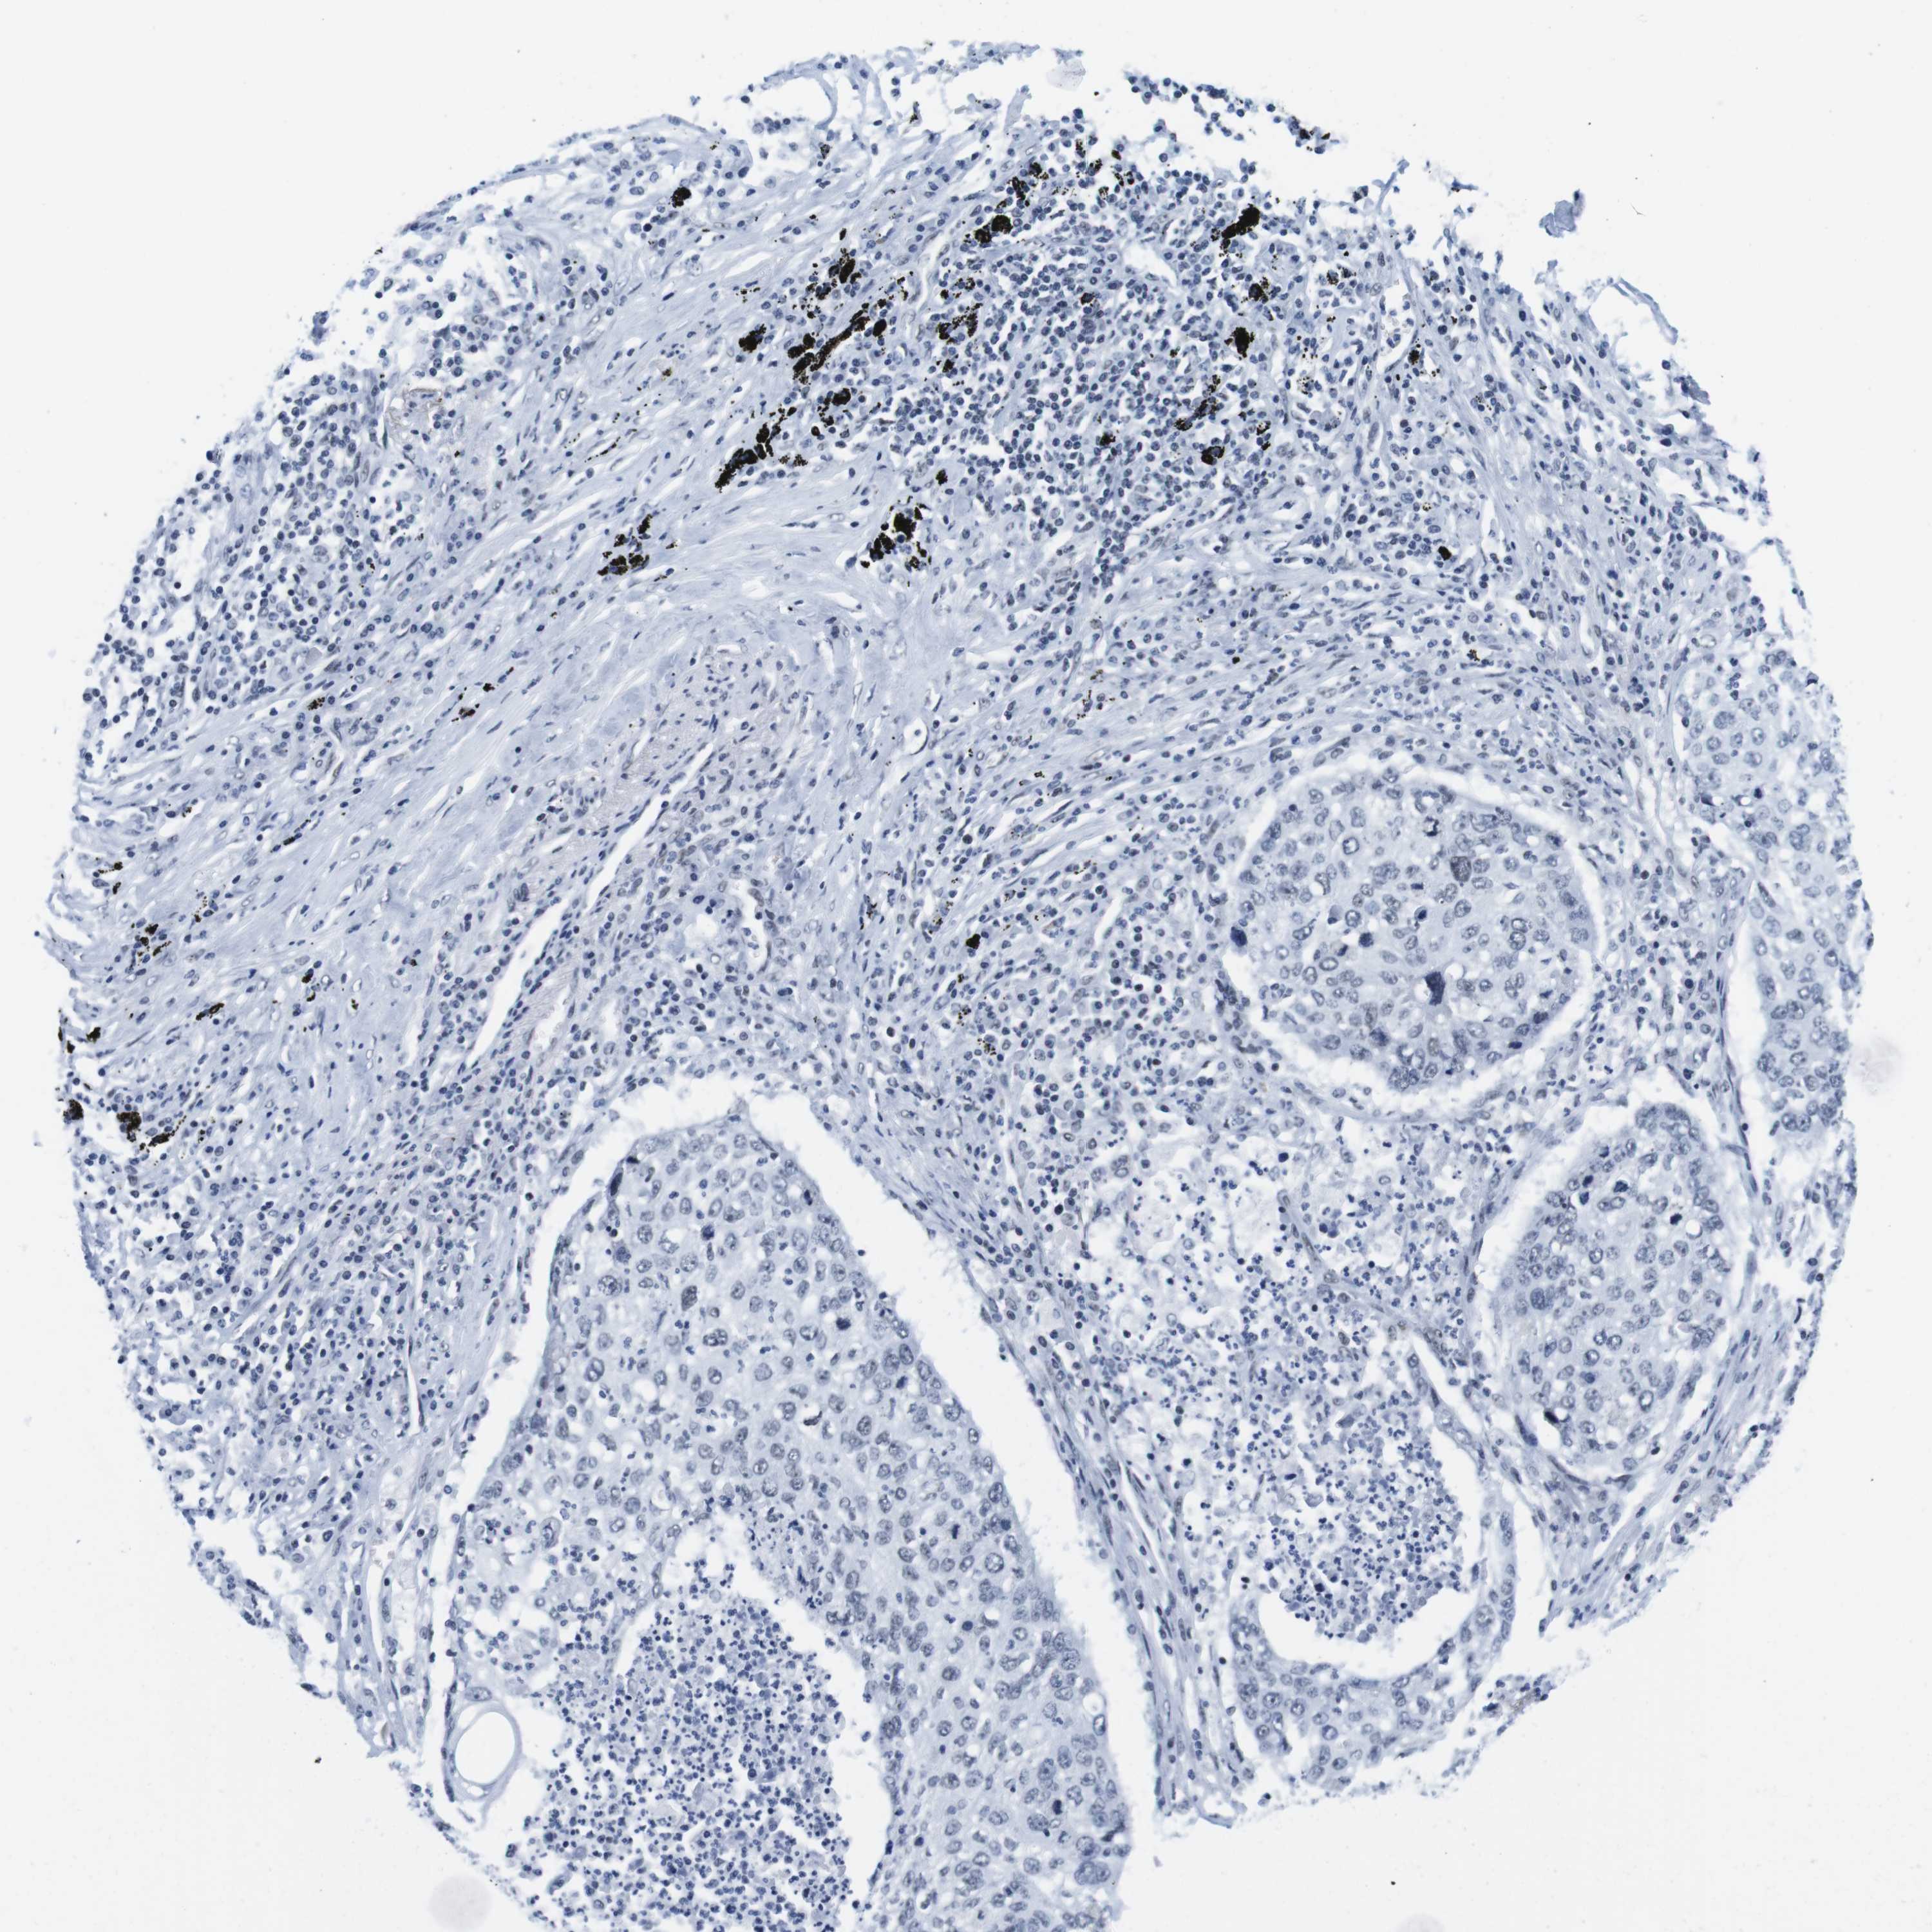

CANCER LUNG CANCER Show tissue menu

IFI16 is potential prognostic, high expression is unfavorable in Lung Adenocarcinoma (validation)

: 182.83

Average pTPM 137.2

Number of samples 105